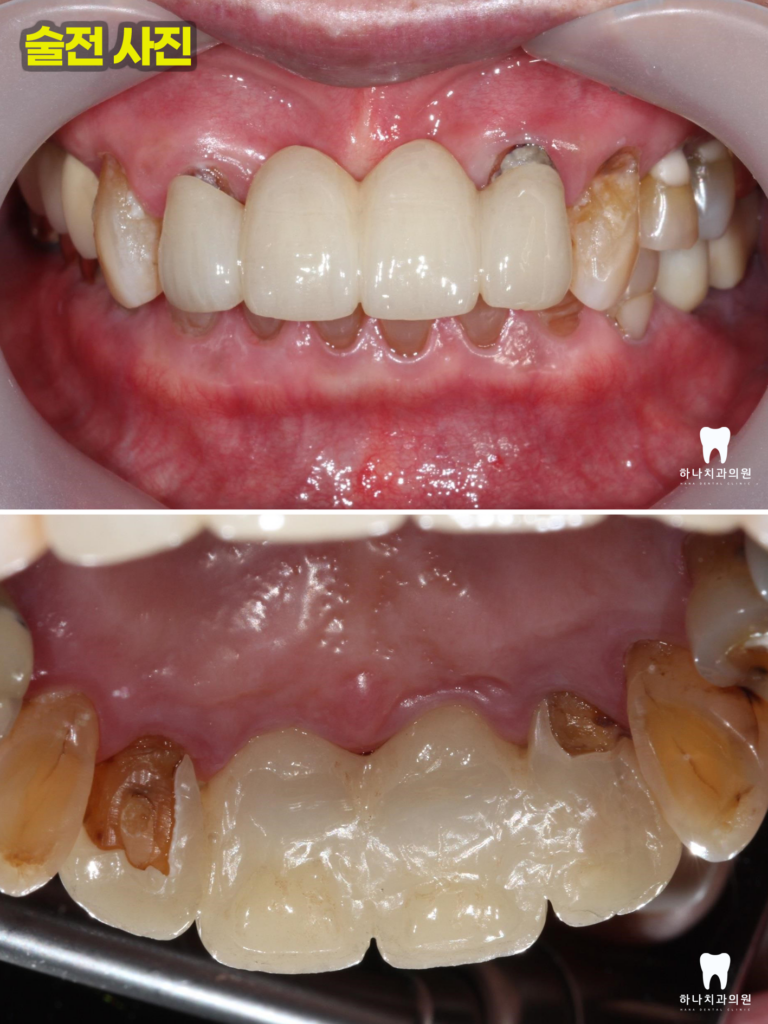

사진에서 보이는 바와 같이

이를 꽉 문 상태에서 아래 앞니가 하나도

보이지 않을 정도의 과한 수직 교합을

보이고 있었는데

그 이유로 부족한 어금니의 높이 때문에

위쪽 앞니가 들어갈 공간이 부족하여

보철의 깨짐과 지대치의 동요도를 보인다고

판단하였습니다.